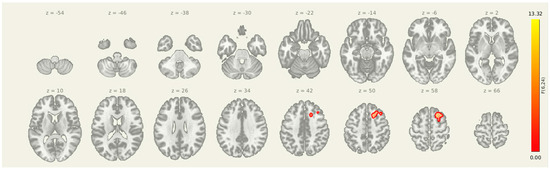

3.3. Amygdala Seed Pre > Post

Following the intervention, seed-to-voxel analysis revealed significantly greater amygdala connectivity at the pre-intervention timepoint compared to post-intervention in two clusters (Figure 3 and Table 4). The first was located in the left postcentral gyrus and somatosensory association area (MNI: +06, −38, +34; cluster size = 382 voxels; p-FDR = 0.0107), and the second was centered in the right superior frontal gyrus (MNI: +22, +22, +54; cluster size = 315 voxels; p-FDR = 0.0171). These results suggest a reduction in amygdala coupling with both sensorimotor and prefrontal regions after the combined rTMS and exercise intervention, consistent with decreased engagement of limbic-driven pain and vigilance networks.

Figure 3.

Seed-to-voxel connectivity reductions from the amygdala following intervention. Significant clusters reflect greater connectivity at pre-intervention compared to post-intervention (Pre > Post), including regions in the left postcentral gyrus and right superior frontal gyrus. Results are thresholded at p-FDR < 0.05 and shown in MNI space.